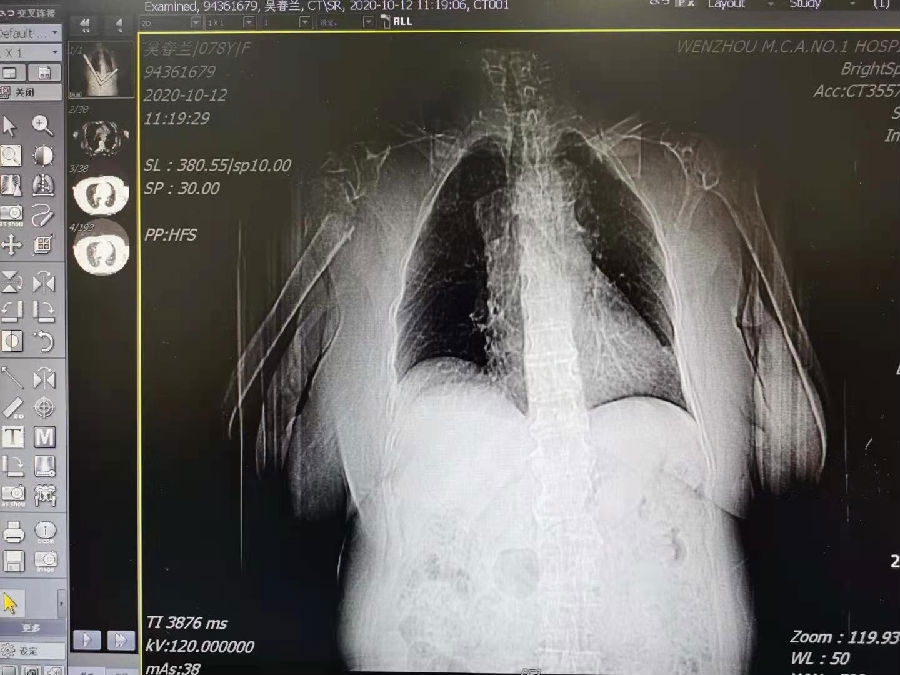

术前肱骨头CT

1、右肱骨近端骨折(Neer 4部分)